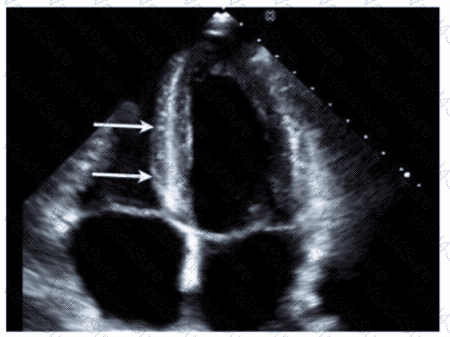

In patients with interrupted aortic arch, which structure allows Wood to flow into the descending aorta?